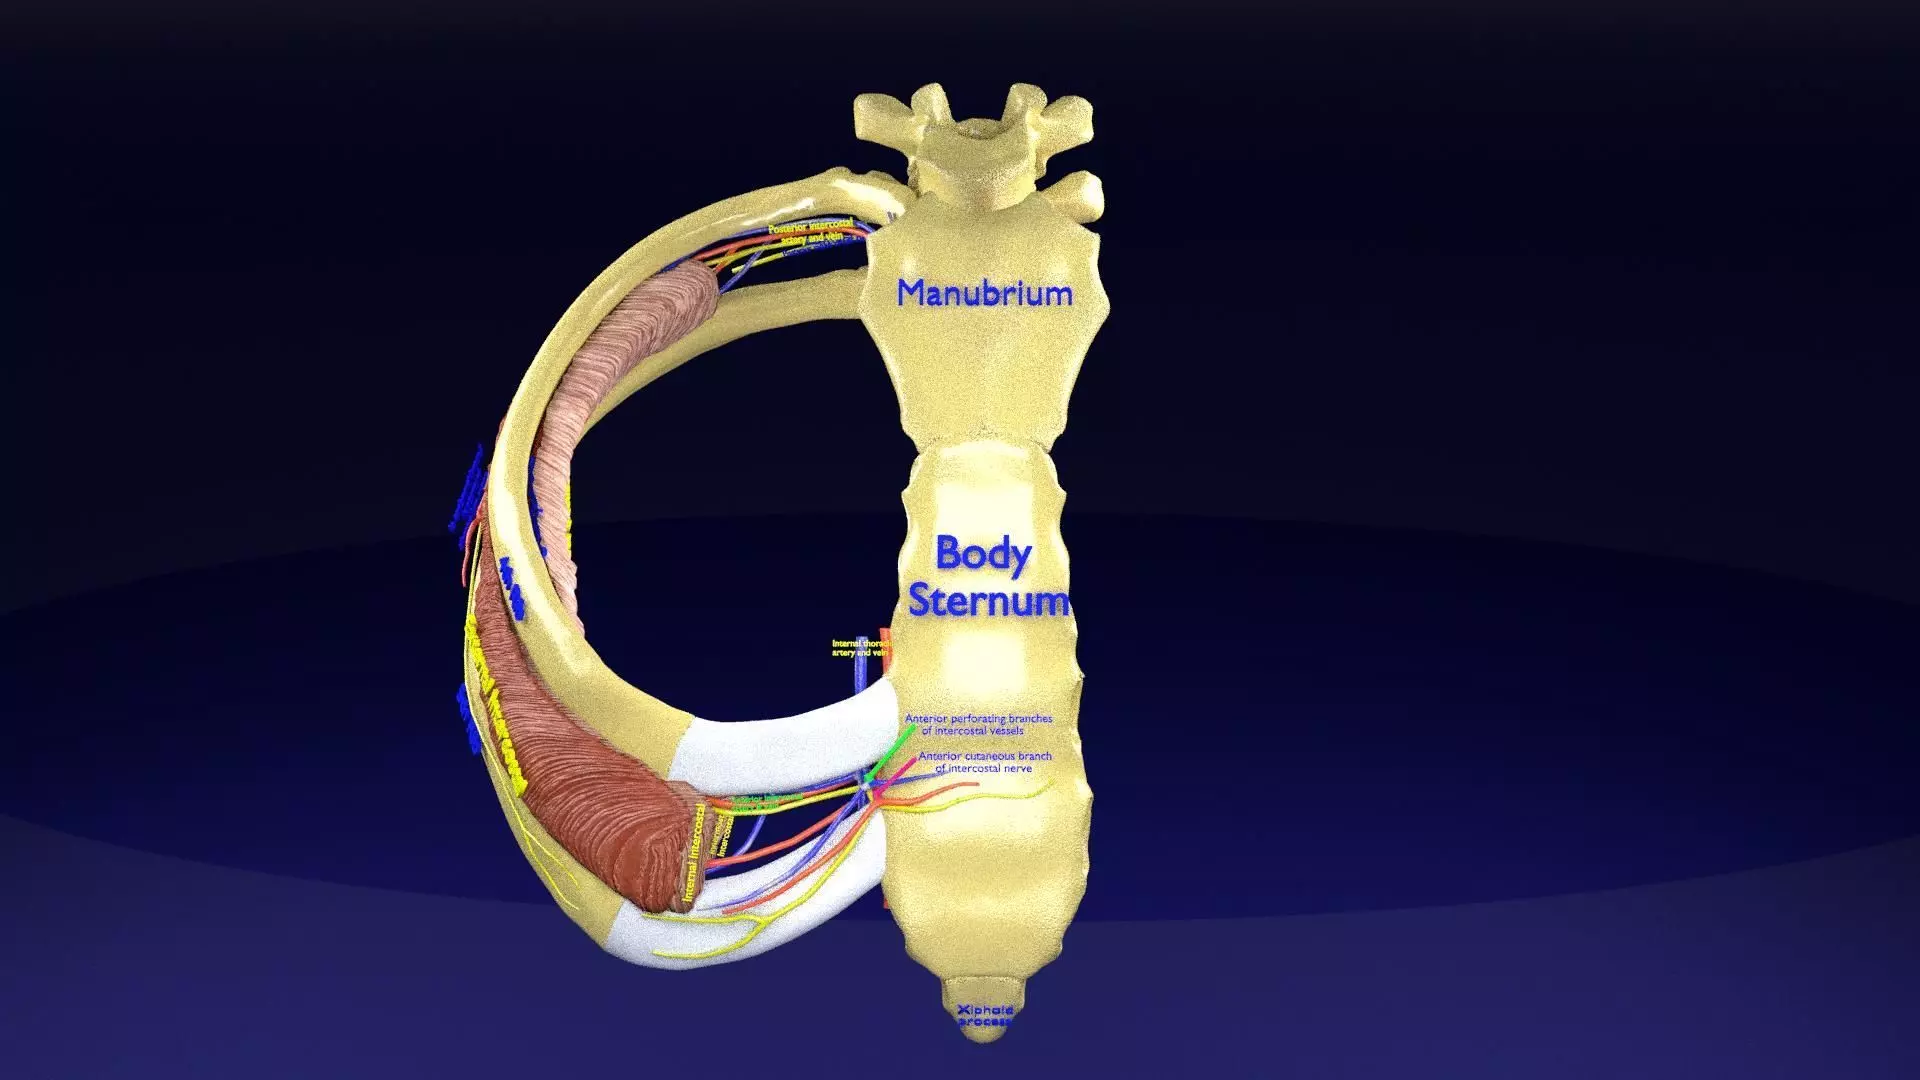

Intercostal ribs muscles nerve vessels labelled.